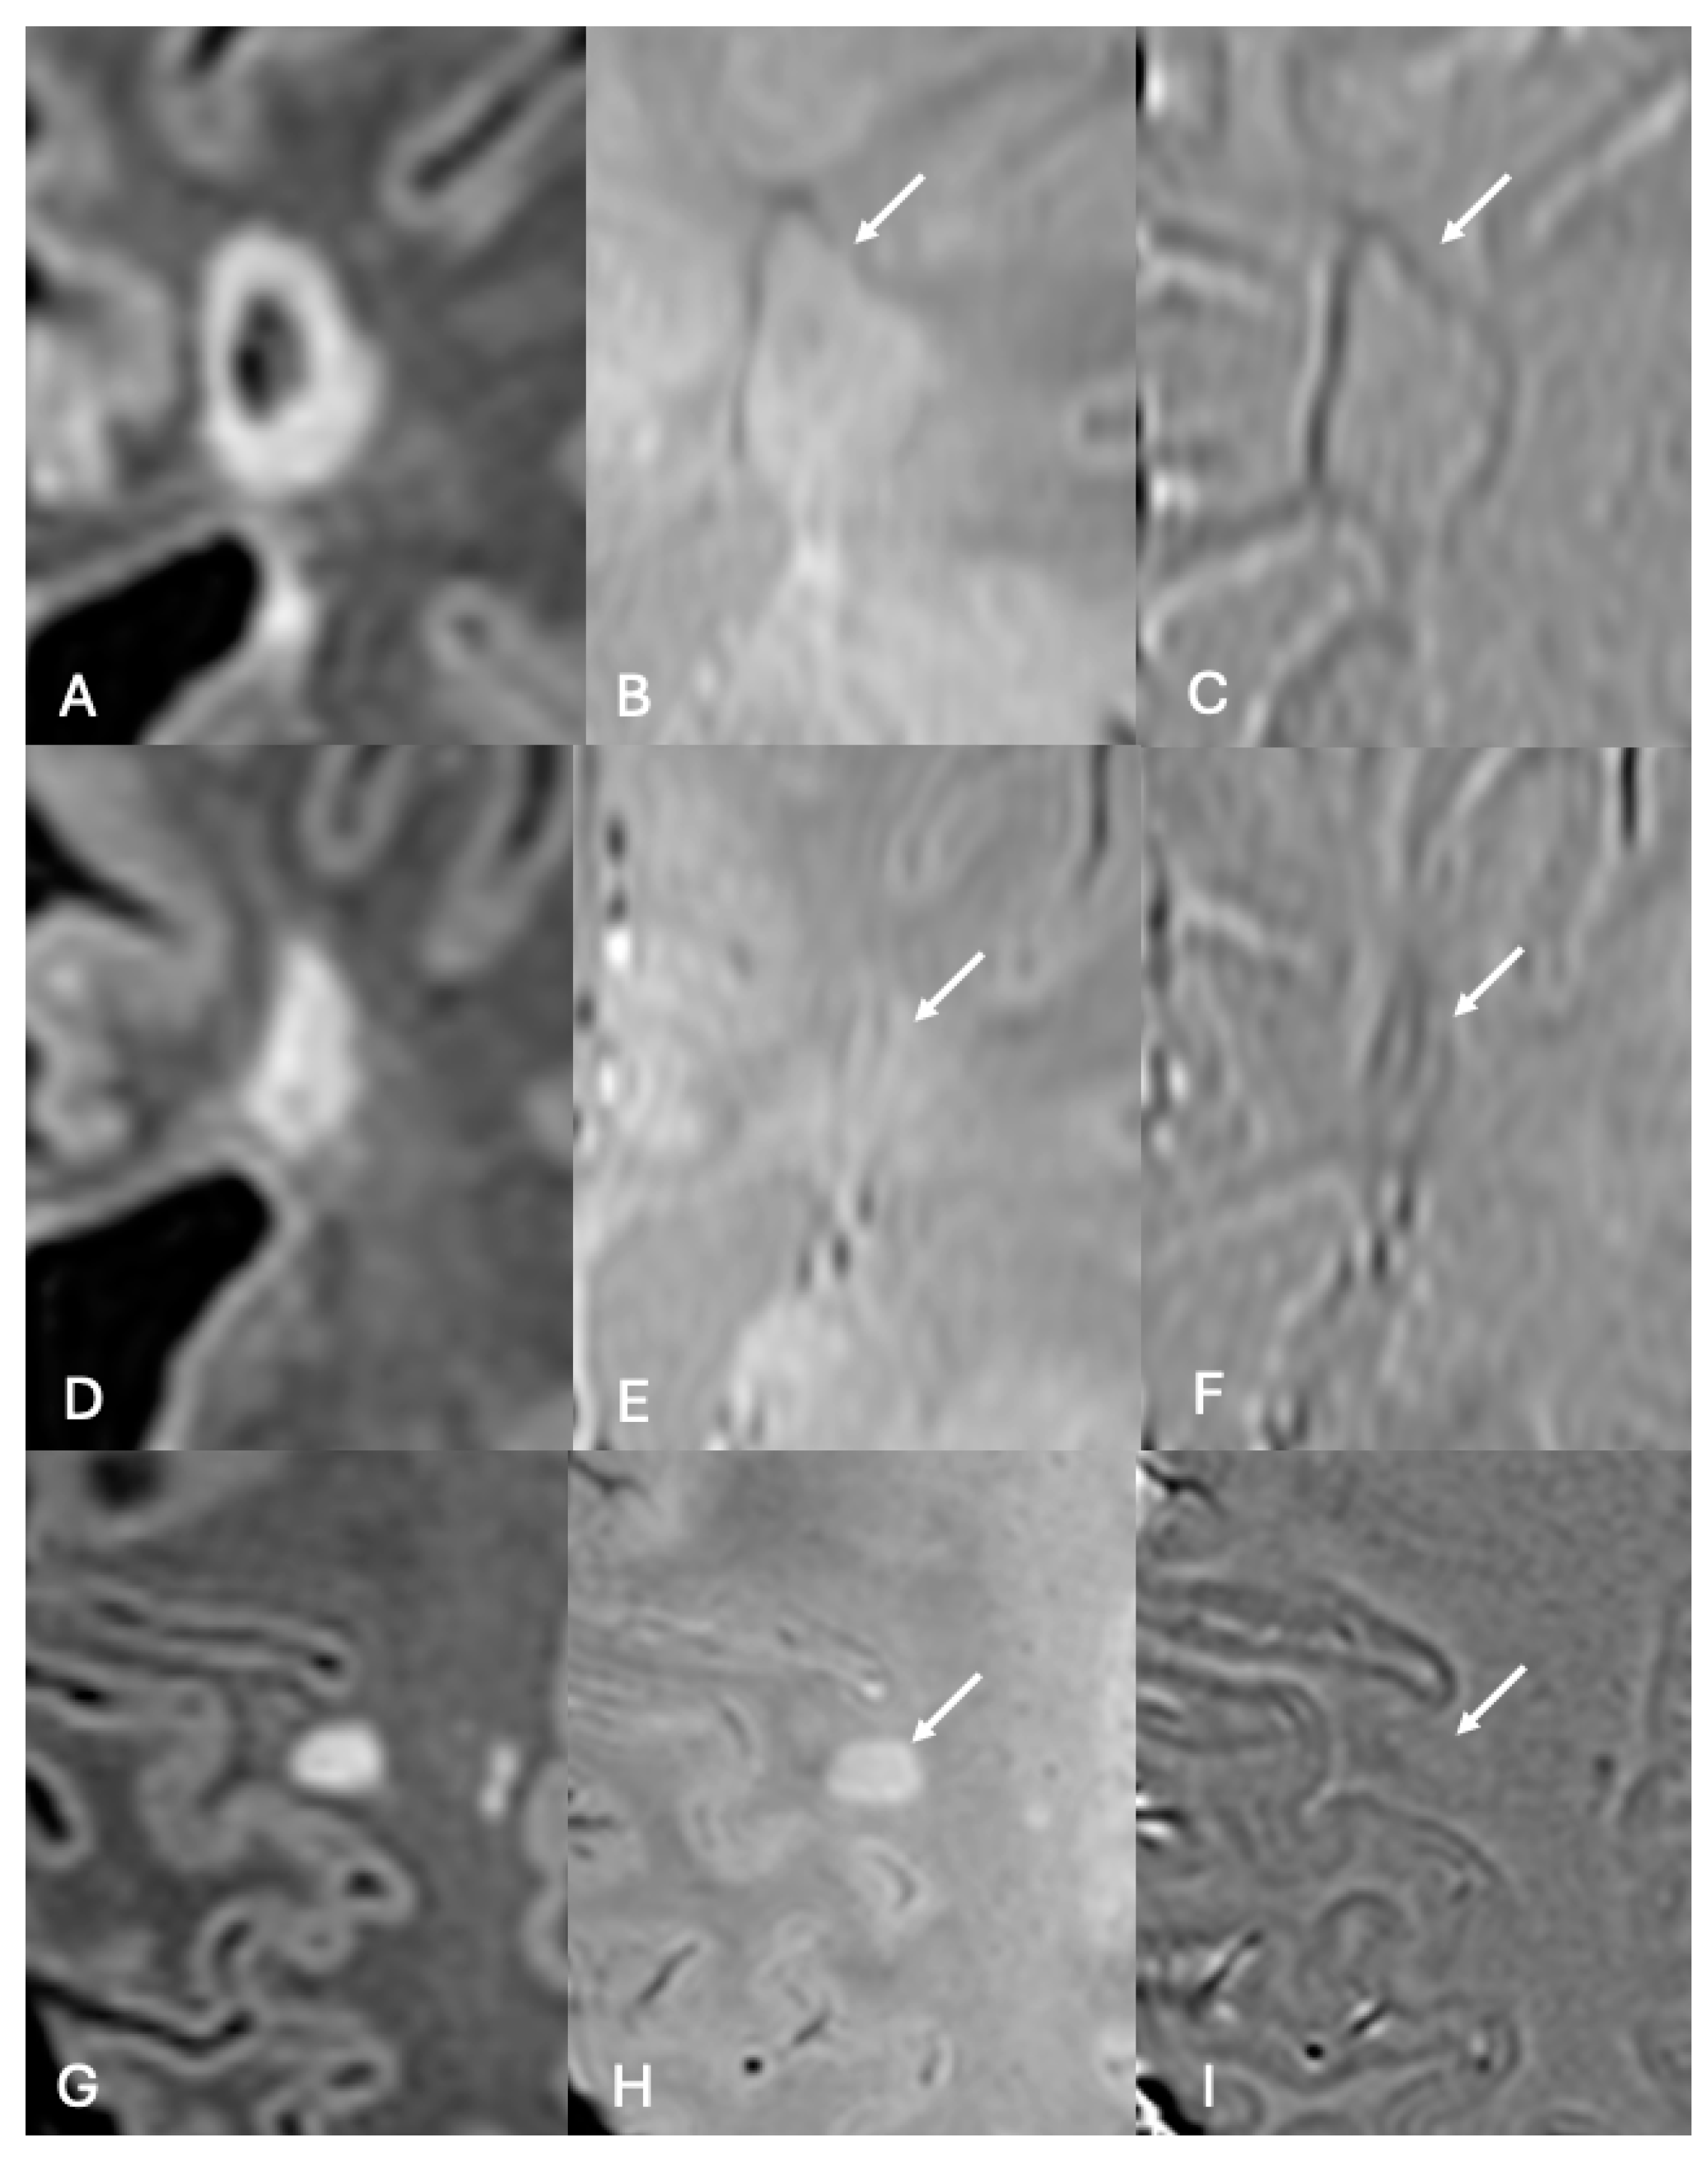

- Absinta, M.; Sati, P.; Fechner, A.; Schindler, M.K.; Nair, G.; Reich, D.S. Identification of Chronic Active Multiple Sclerosis Lesions on 3T MRI. AJNR Am. J. Neuroradiol. 2018, 39, 1233–1238. [Google Scholar] [CrossRef]

- Maggi, P.; Sati, P.; Nair, G.; Cortese, I.C.M.; Jacobson, S.; Smith, B.R.; Nath, A.; Ohayon, J.; van Pesch, V.; Perrotta, G.; et al. Paramagnetic Rim Lesions are Specific to Multiple Sclerosis: An International Multicenter 3T MRI Study. Ann. Neurol. 2020, 88, 1034–1042. [Google Scholar] [CrossRef]

- Absinta, M.; Sati, P.; Masuzzo, F.; Nair, G.; Sethi, V.; Kolb, H.; Ohayon, J.; Wu, T.; Cortese, I.C.M.; Reich, D.S. Association of Chronic Active Multiple Sclerosis Lesions With Disability In Vivo. JAMA Neurol. 2019, 76, 1474–1483. [Google Scholar] [CrossRef]

- Hemond, C.C.; Reich, D.S.; Dundamadappa, S.K. Paramagnetic Rim Lesions in Multiple Sclerosis: Comparison of Visualization at 1.5-T and 3-T MRI. AJR Am. J. Roentgenol. 2022, 219, 120–131. [Google Scholar] [CrossRef] [PubMed]